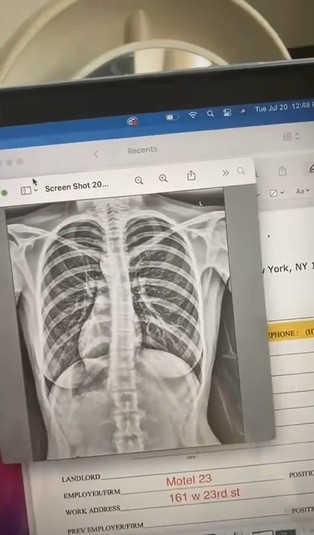

Врач сказал американке, что, скорее всего, у нее какая-то легочная инфекция, и отправил на рентген грудной клетки. Результаты обследования оказались совершенно неожиданными: Клэр узнала, что ее сердце расположено не слева, как у большинства других людей, а справа. Когда доктор сообщил девушке эту новость, она подумала, что он просто шутит, пишет The Mirror.

«Врач объяснил, что это называется декстрокардией, и что я должна сообщить о своем состоянии моему лечащему врачу. Когда я услышала об этом, я все время повторяла: «Вы это серьезно?» Я была просто в шоке и не понимала, почему я узнала об этом только в 19 лет», — рассказала Клэр.

Декстрокардия — это чрезвычайно редкая аномалия развития, при которой большая часть сердца расположена с правой стороны груди. С таким расположением сердца рождается менее одного процента людей, и обычно это состояние не опасно для жизни.